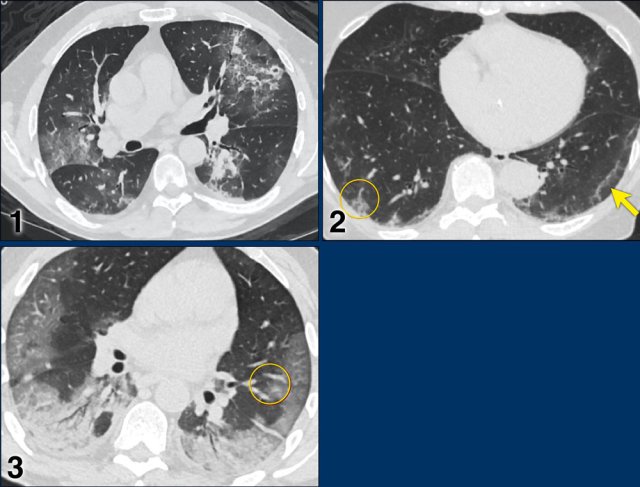

Examples of CO-RADS 3. Click to enlarge. Examples of CO-RADS 3. Click to enlarge.

CORADS 3

COVID-19 unsure or indeterminate.

CT abnormalities indicating infection, but unsure whether COVID-19 is involved, like widespread bronchopneumonia, lobar pneumonia, septic emboli with ground glass opacities.

Case 1.

One day complaints. CT: Unifocal GGO. PCR negative.

Case 2.

CT: Unifocal GGO (circle).

Case 3.

CT: Unifocal GGO (arrow).

Case 4.